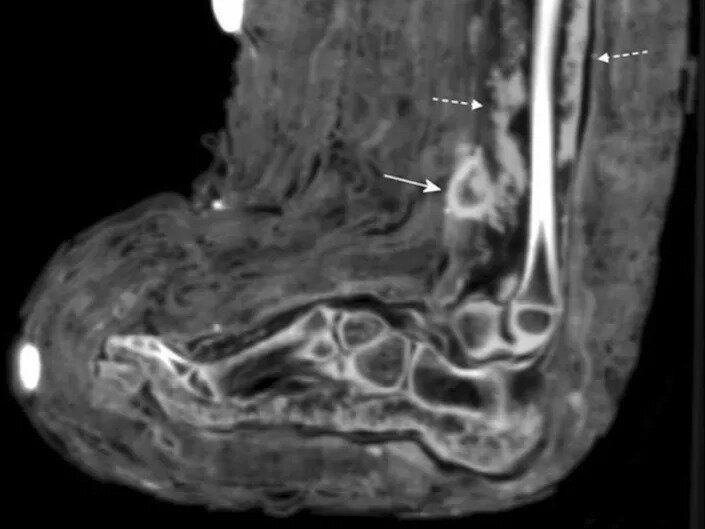

در سیتی اسکن مومیایی پانسمان زخم با «فلش پیوسته» و چرک درون زخم با «فلش مقطع» نشان داده شده است

زینک و همکارانش هنگامی در حال انجام سیتی اسکنهای معمول بر روی مومیاییها بودند، این پانسمان را کشف کردند. سیتی اسکن نشانههایی از وجود چرک را هم در زخم نشان میداد.